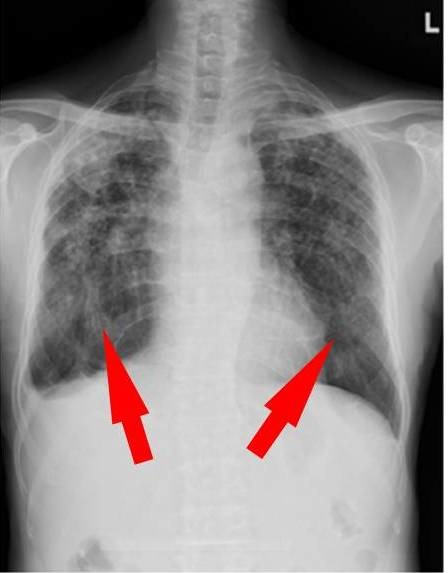

工人長時間(通常為數年)吸入小顆粒的結晶二氧化矽,會發展成矽肺病,這是一種嚴重的肺部疾病。

許多工人的研究調查了暴露結晶二氧化矽與不良健康影響之間可能的關係。這些研究顯示,工人長時間(通常為數年)吸入小顆粒的結晶二氧化矽,會發展成矽肺病(silicosis),這是一種嚴重的肺部疾病。結晶二氧化矽是導致矽肺病的唯一化合物。工人的研究也證實,二氧化矽會導致慢性阻塞性肺病(COPD)、肺癌、腎衰竭、自體免疫疾病,並增加對結核病的易感性。